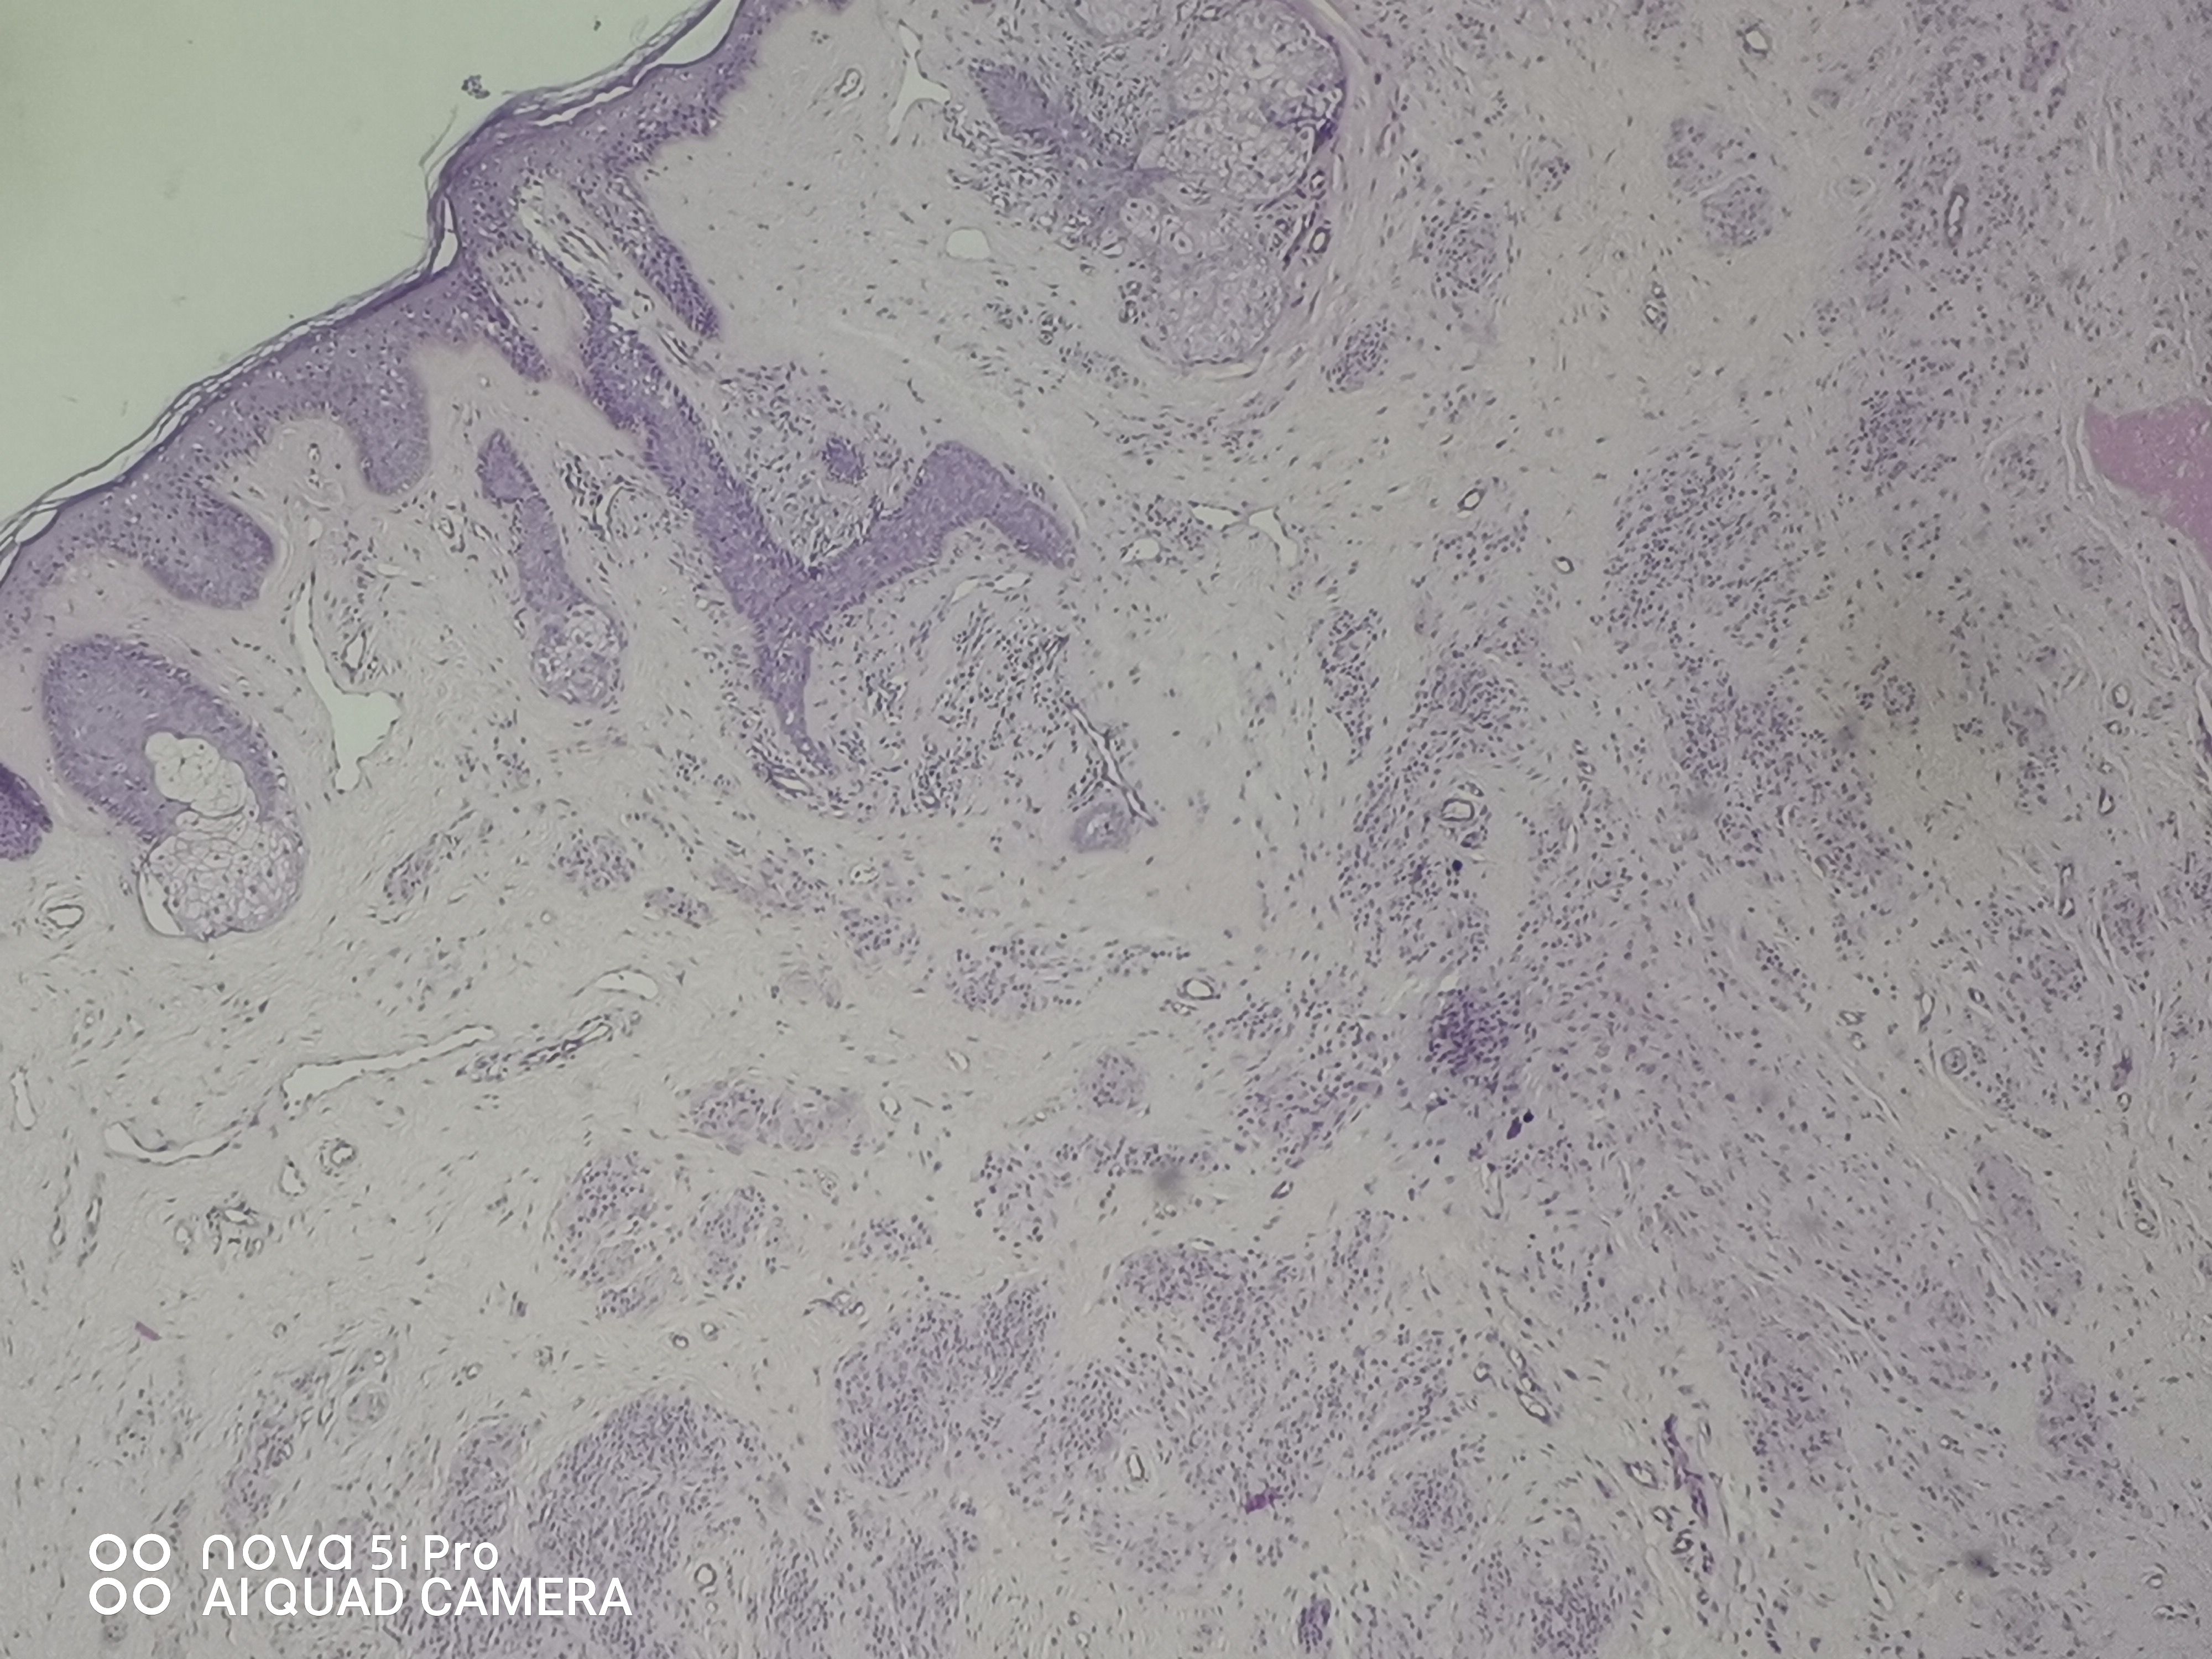

请老师们看看,右外耳道肿块,皮内痣?有问题吗?

性别

女

年龄

41岁

临床诊断

待查

一般病史

发现右外耳道肿块41年

标本名称

右外耳道肿块

大体所见

组织一块,大小约0.9*0.8*0.6cm,对半切开,灰白质中。全取

图2

皮内痣

皮内痣,报切缘